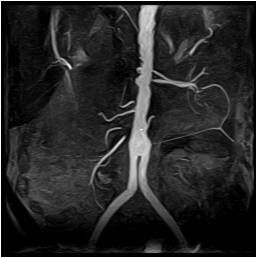

Исследование брюшной полости

Ввиду наибольшей доступности, быстроты исследования и разрешения, достаточного для выявления большинства патологий, для сканирования брюшной полости и забрюшинного пространства используется компьютерная ангиография на мультиспиральном томографе. Этот метод позволяет:

- выявить причину мезентериальной ишемии;

- успешно определяют патологии печеночных сосудов (например,тромбоз воротной вены);

- КТ ангиография почек показывает аномалии развития и варианты ответвления почечных артерий, их стенозы и окклюзии (например, опухолевые);

- выявляет расширение или окклюзию тромбом полой вены;

- оценить состояние брюшной аорты (расслоение, коарктация, аневризма).

МР-ангиография брюшной полости применяется главным образом для определения распространенности ракового поражения и выявления мелких метастазов.